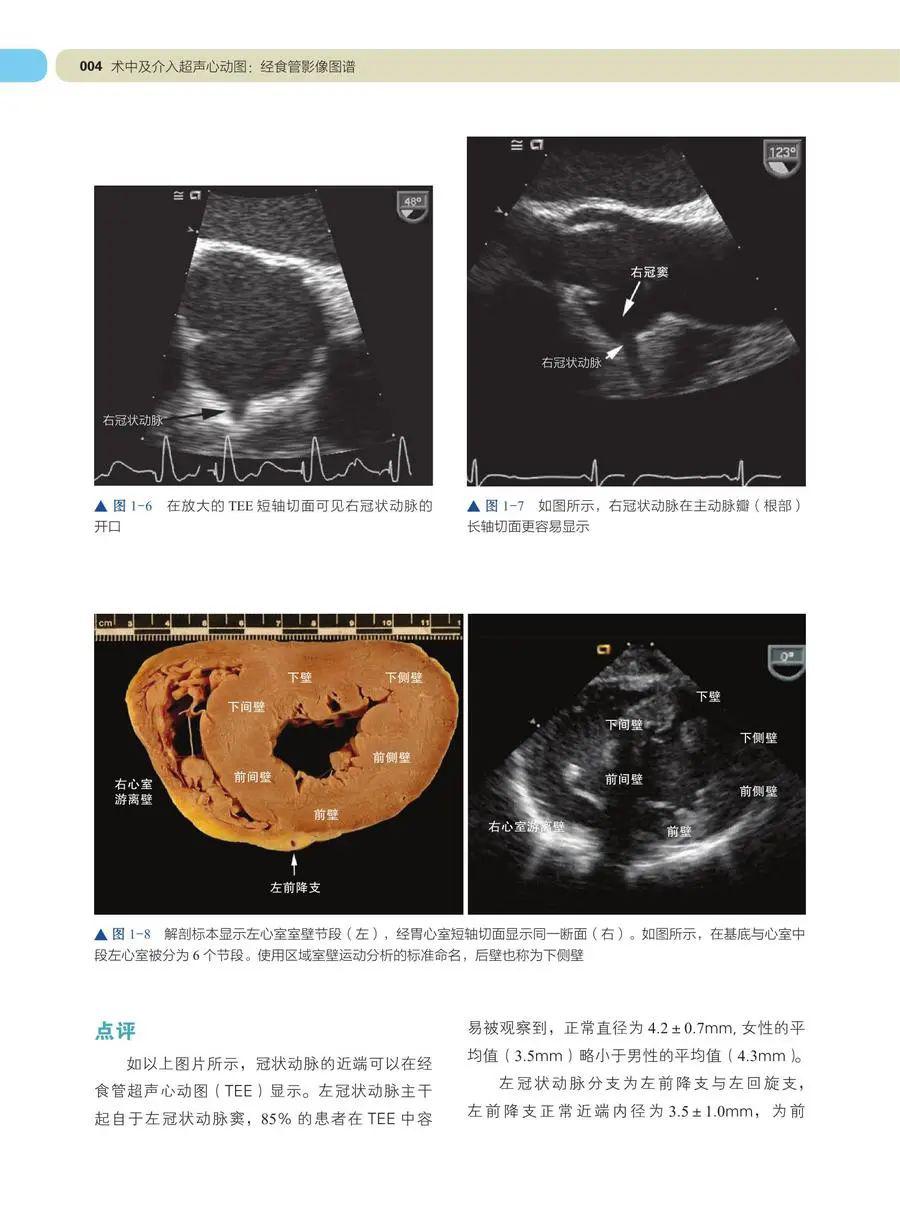

经食道超声心动图,就是平常人们所说的食道心脏彩超,英文简称tee

经食管超声心动图的临床应用 (transesophageal echocardiography tee